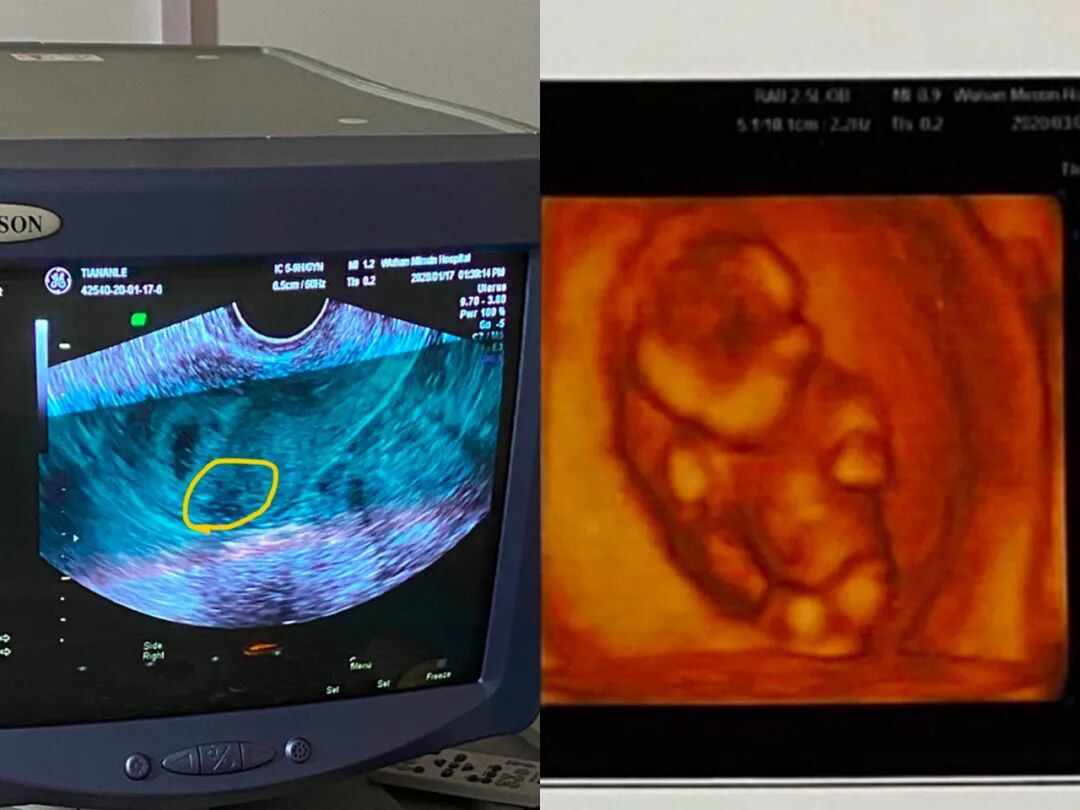

宝宝产检的图